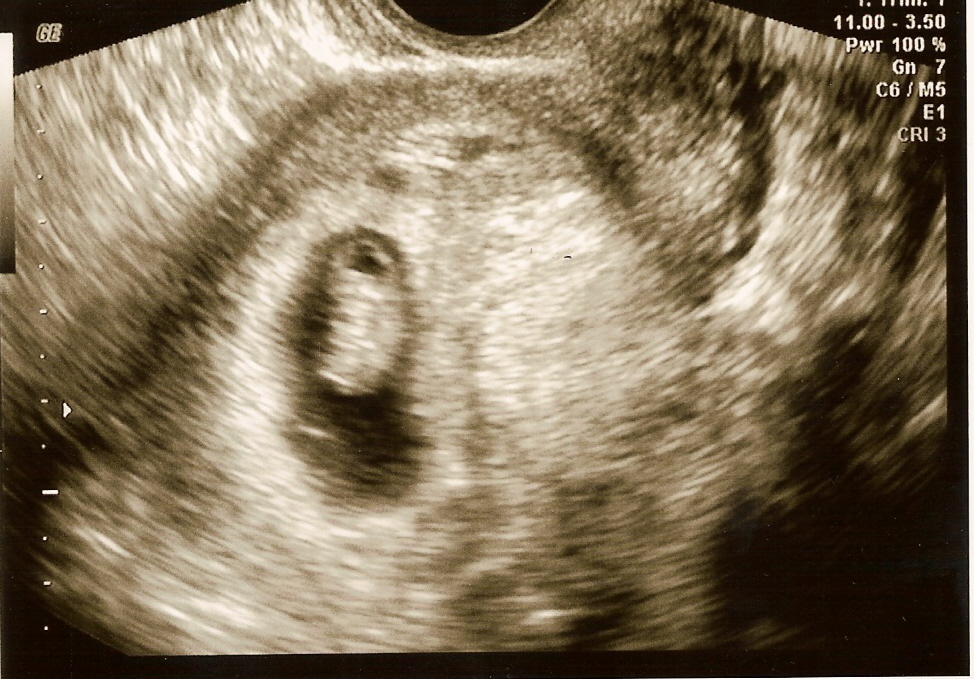

jan-5-09-ultrasound-imageAll we can do is say “Thank You” to any and all who have been praying for us. Regular fans and readers will recall being asked to pray for Teresa and our unborn child some weeks back. In 2002 and 2004 we had early term miscarriages, and were uncertain about this pregnancy from the very start. Pictured at left are two ultrasound images, the top from Jan 5 (9 weeks) and the other from Feb 2 (13 weeks). The baby is now 6.51 cm, with a fetal heartbeat of 162 bpm. It is too efeb-2-09-ultrasound-imagearly to determine gender, and atour next appointment (17 weeks) we will probably still have to wait.

If you click on the thumbnail image it will open full size. They were scanned at only 200 dpi so they could be uploaded more easily.